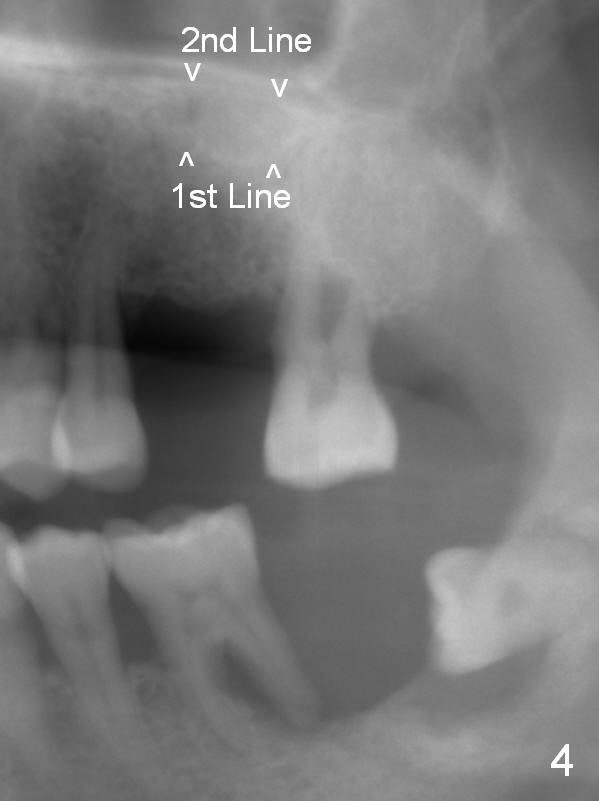

Implant placement at #31 reveals that bone width (bucco-lingual) is not a problem for a 64-year-old man. He requests implant placement at #7 and 14 (Fig.1,3), because the upper flipper has been lost. He wants to make sure that the implant at #7 does not cause the pain at #6. In fact the flipper appears to have lead to caries (Fig.2 *) and periapical radiolucency (<) at #6. RCT is rendered at #6 prior to a 1-piece implant at #7 (Fig.1). Since bone height is sufficient, the implants do not have to penetrate the nasal floor (Fig.1 v) or the sinus floor (Fig.3 <) unless the bone density is low. Prepare implant positioner of 4 mm to determine whether the ridge is wide to hold a 3.8 or 4 mm implant. Take preop photos to show the ridge width.

Re-analysis of #14 edentulous area reveals slightly unfavorable crown/implant ratio if the implant reaches the 1st line of the sinus floor (Fig.4). A 5x13 mm implant may invade the 1st line (Fig.5). Therefore the depth of osteotomy using 4.8 mm Magic Drill is 9-10 mm (Fig.6 green), followed by Magic Sinus Lifter, unless the bone density is high.